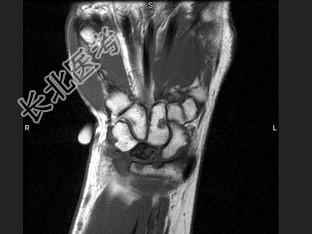

- 单项选择题女,41岁, 纺织工,腕部疼痛无力数周, 结合CR和MR,最可能的诊断是 ( )

B、月骨缺血坏死